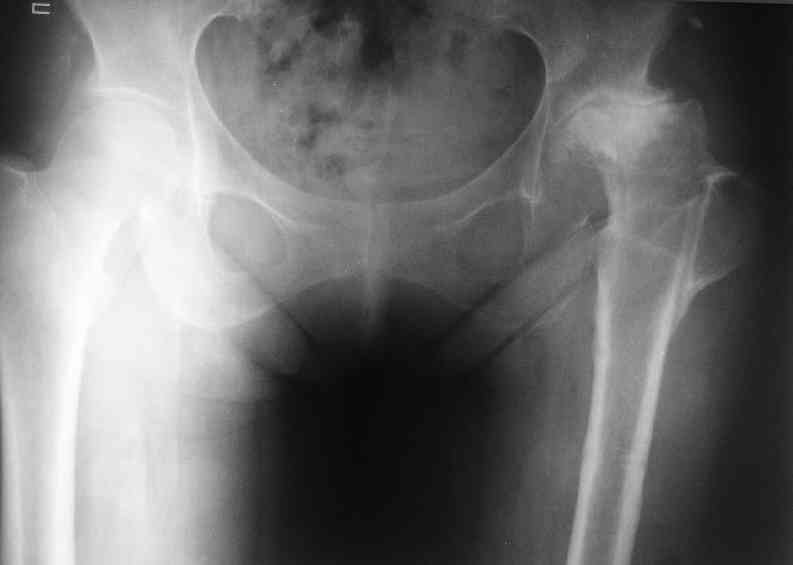

AV> опираясь на стул. На ногу не наступает. Укорочение 8 см. Иногда

А за счет чего такое укорочение? По снимку не видно соответствующего дефекта. Ну плюс приводящая контрактура - но все равно как-то уж больно много. Может, сделать снимки и таза обзорный с обоими проксимальными отделами бедра, и коенный суставов с приложенной линейкой какой?

Судя по снимку, максимум истинное укорочение около 4 см, что может быть коррегировано интраоперационно. Вопрос в другом: куда ставить ацетабулярный компонент в истинную или во вновь сформированную ( впадина диспластичная).

Невозможно не согласиться с Анатолием, чтобы заниматься адекватным планированием как минимум прямая проекция таза должна быть сделана, как

максимум для оценки состояния мышц( насколько реально возможно низвести бедро) прямая проекция таза с тракцией за больную ногу.

The X ray that you provided does not show 8 cm of shortening. Perhaps you could send one showing the whole pelvis and proximal femurs.

I agree with Dr Eid's comments. The origin of the 8 cm leg length difference is a puzzle. Is this a clinical measurement? In that case contracture of the joint might affect the measurement. Can we see an AP pelvis to include both hip joints (including a calibration object with a known length) so that the difference in leg lengths that can be ascribed to the hip deformity and bony reabsorption can be measured. This sort of xray will help with templating for the TJR also. I would be very tempted to do a one stage procedure and accept some shortening. Shoe lifts should take care of a 3-4 cm difference.

До травмы проблем с ногой не было. Укорочения, болей и т.п. не отмечал. Сегодня перемерял укорочение - меньше 7 см намерять не

По уровню малых вертелов (с учетом рентгеновского увеличения) получается 5 см. Клинически ногу низвести путем тракции невозможно. Из движений - сгибание до 40*, остальные движения "символические".

Ортопедическое укорочение пострадавшей ноги может быть и 7, и 10 см. за счет контрактур в тазобедренном суставе, а вот истинное укорочение, судя по представленным рентгенограммам, вряд ли больше 4 см.